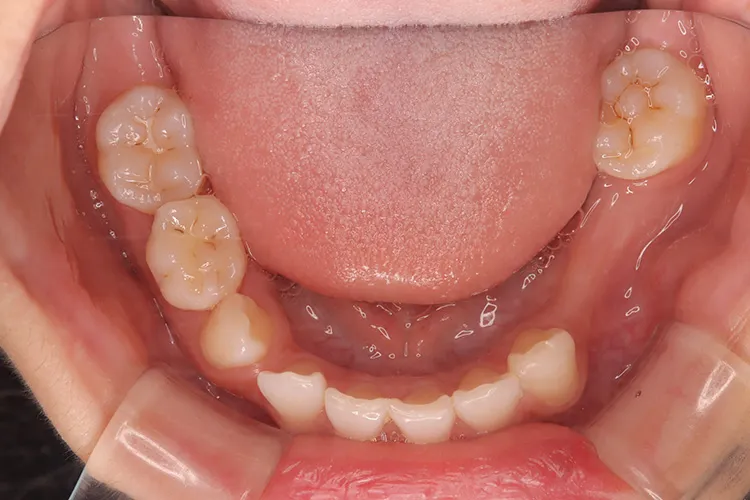

症例9/

永久歯先天欠如

- 治療期間

- 3ヶ月

- 費用

- 147万円(税込)

治療前

治療後

レントゲン画像

治療内容

20歳の患者様の永久歯先天欠如のケースです。右上4・右下5・左下45の他、第二大臼歯も3本先天欠如していました。年齢も若いため、歯を傷める可能性の高いブリッジは選択されず、長期間安定して機能するインプラントを選択されました。このように若年者で永久歯が先天欠如しているケースにも応用できます。